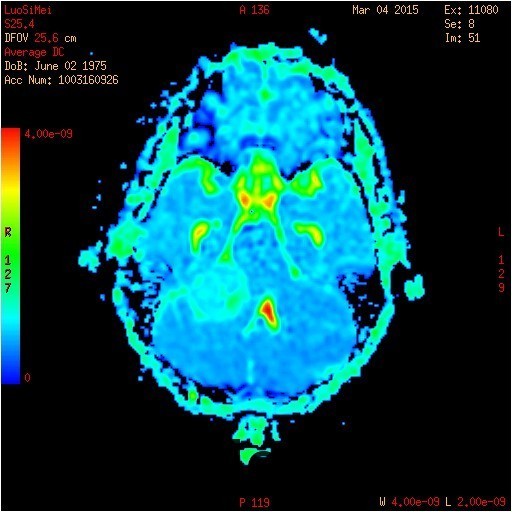

查体:神志清醒,查体合作。双眼视物模糊,眼球运动无明显异常。双侧瞳孔等大等圆,直径3mm,对光反射灵敏。 辅查:头部CT示:右侧桥小脑角区占位,考虑听神经瘤可能,并梗阻性脑积水。建议进一步MRI检查;头部MR示:右侧桥小脑角区占位,考虑为听神经瘤,并梗阻性脑积水;DTI示脑桥、桥臂及右侧桥小脑角白质纤维束受压移位。

随访:术后病理结果提示:(右侧桥小脑角处肿物)肿瘤由梭形细胞构成,可见疏区及密切,部分细胞呈栅栏状排列,细胞有异型性,核分裂可见,间质有散在淋巴细胞浸润,结合免疫组化结果,符合神经鞘瘤。 讨论:听神经瘤是桥小脑区最常见的肿瘤,也是最常见的脑神经瘤,绝大多数病理类型为神经鞘瘤。下面结合本例影像学习一下其影像表现:首先就是部位,发生于桥小脑区的占位第一反应是听神经瘤,而且和岩骨是呈锐角相交,该征象可以和发生于该部位脑膜瘤鉴别。另外,肿瘤沿听神经长如,导致内听道扩大也是一个重要征象。增强扫描可见明显强化,这可以和发生于该部位的胆脂瘤鉴别。